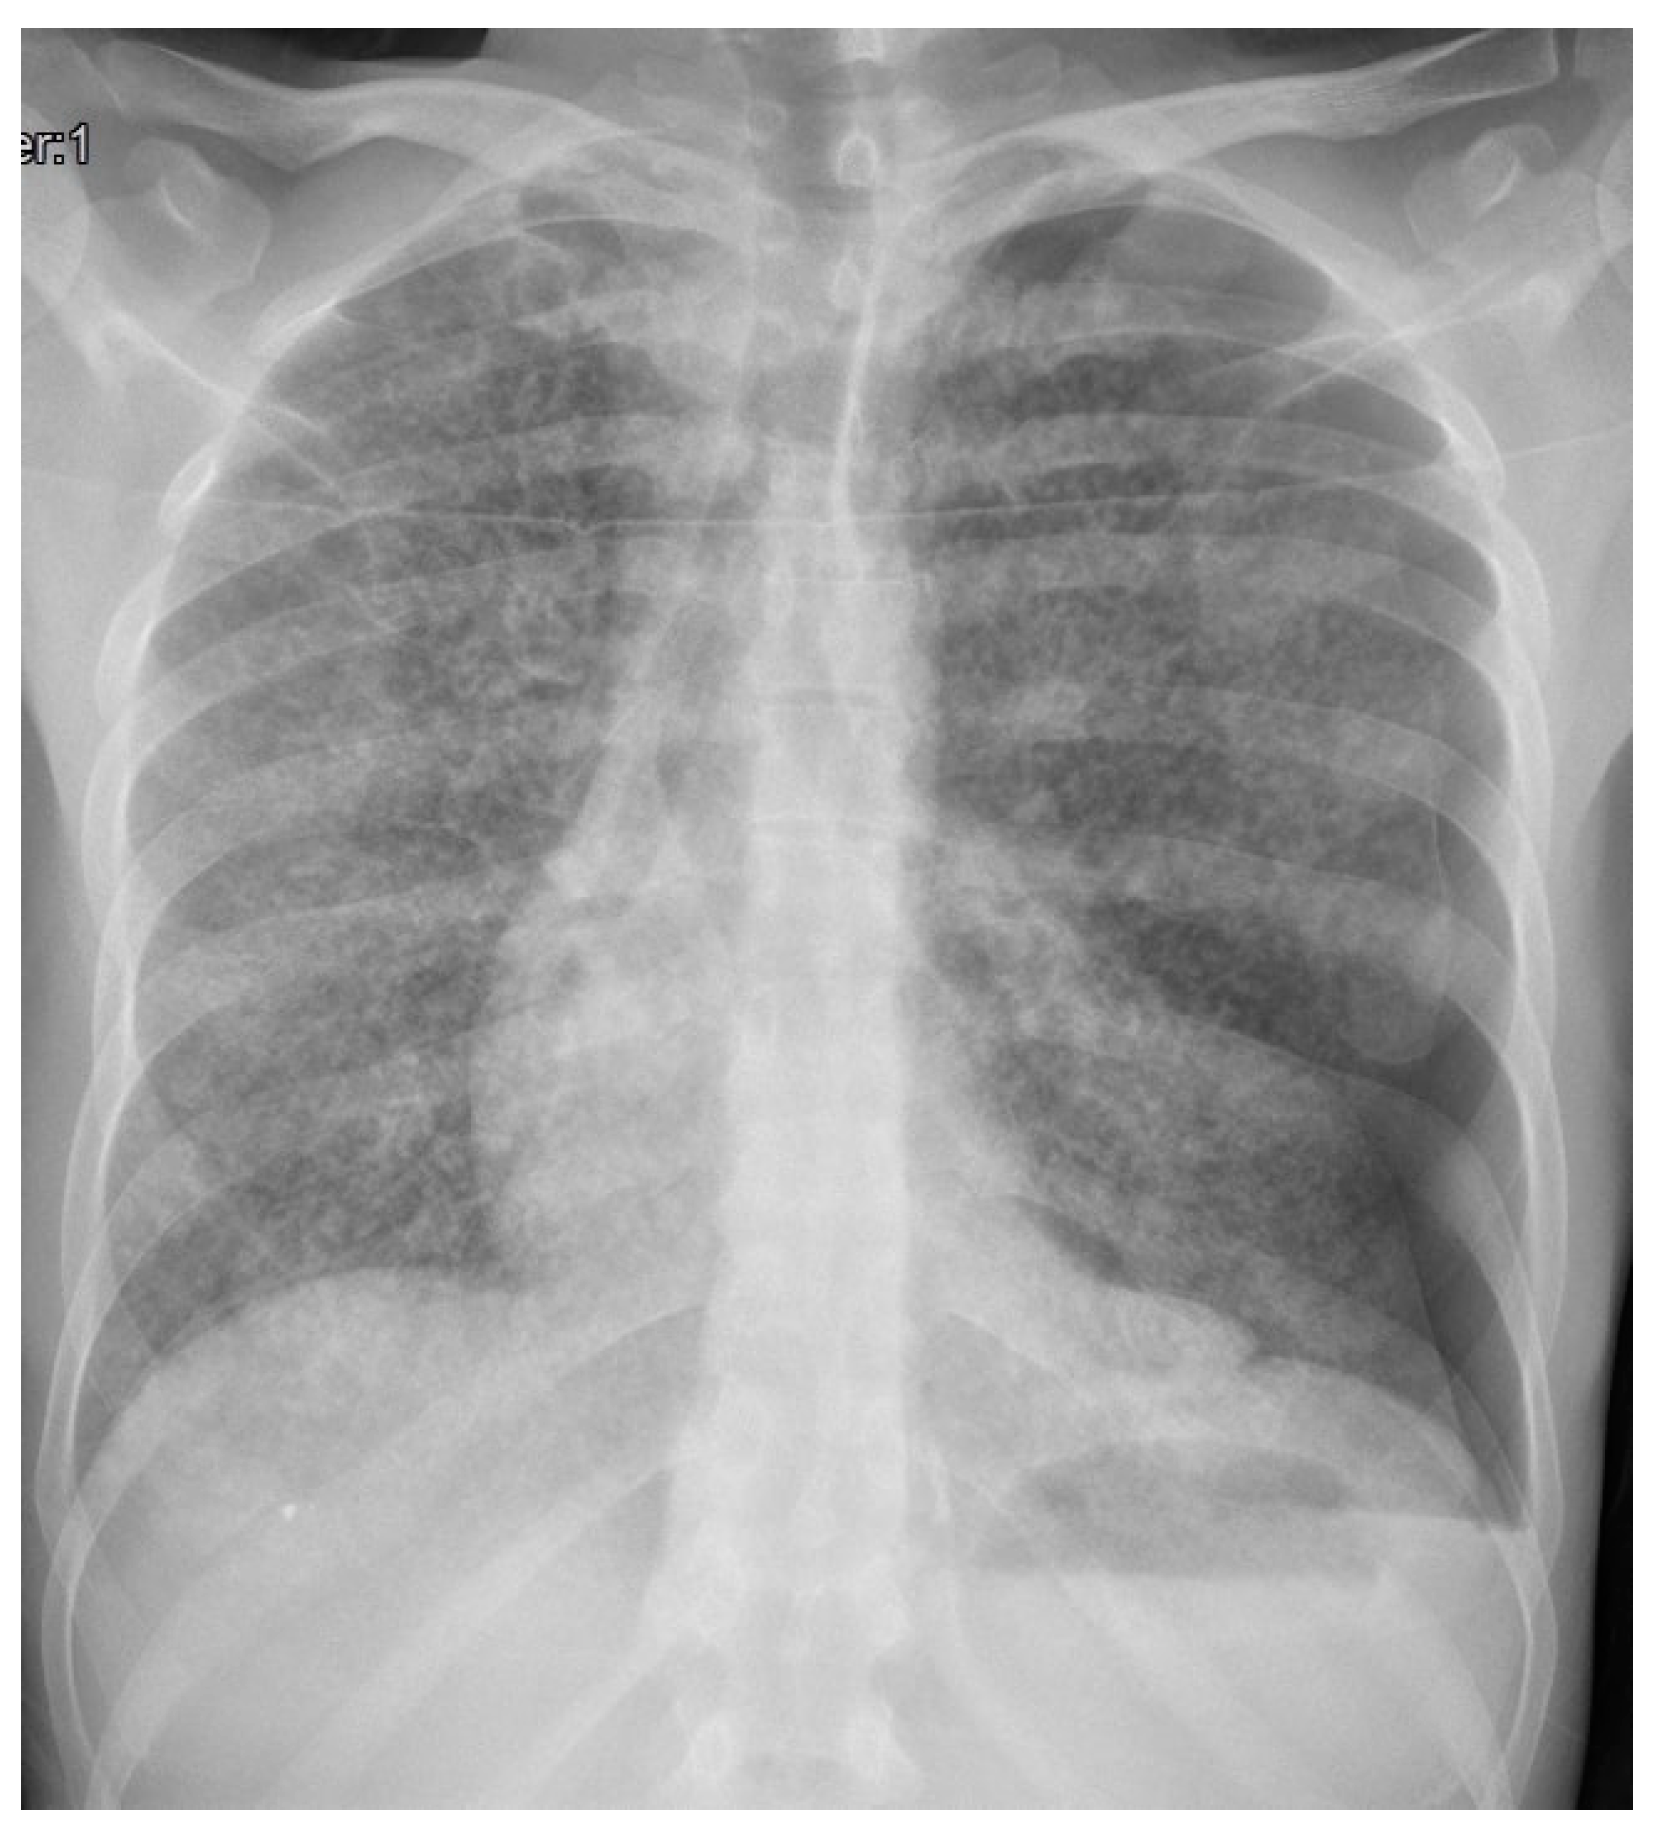

3. Case Description

4. Clinical Case Management